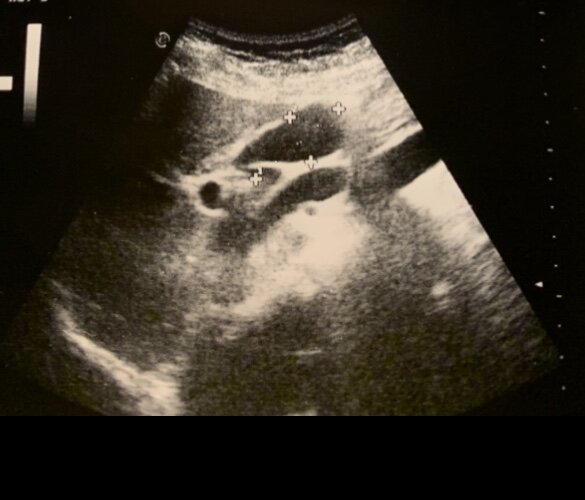

Для уточнения причины выявления желчи в желудке рекомендуется выполнение УЗИ органов брюшной полости и рентген желудка с бариевой взвесью.

УЗИ органов брюшной полости позволяет выявить косвенные признаки дискинезии желчевыводящих путей, патологию желчного пузыря, желчных протоков, оценить функцию желчного пузыря с желчегонным завтраком.